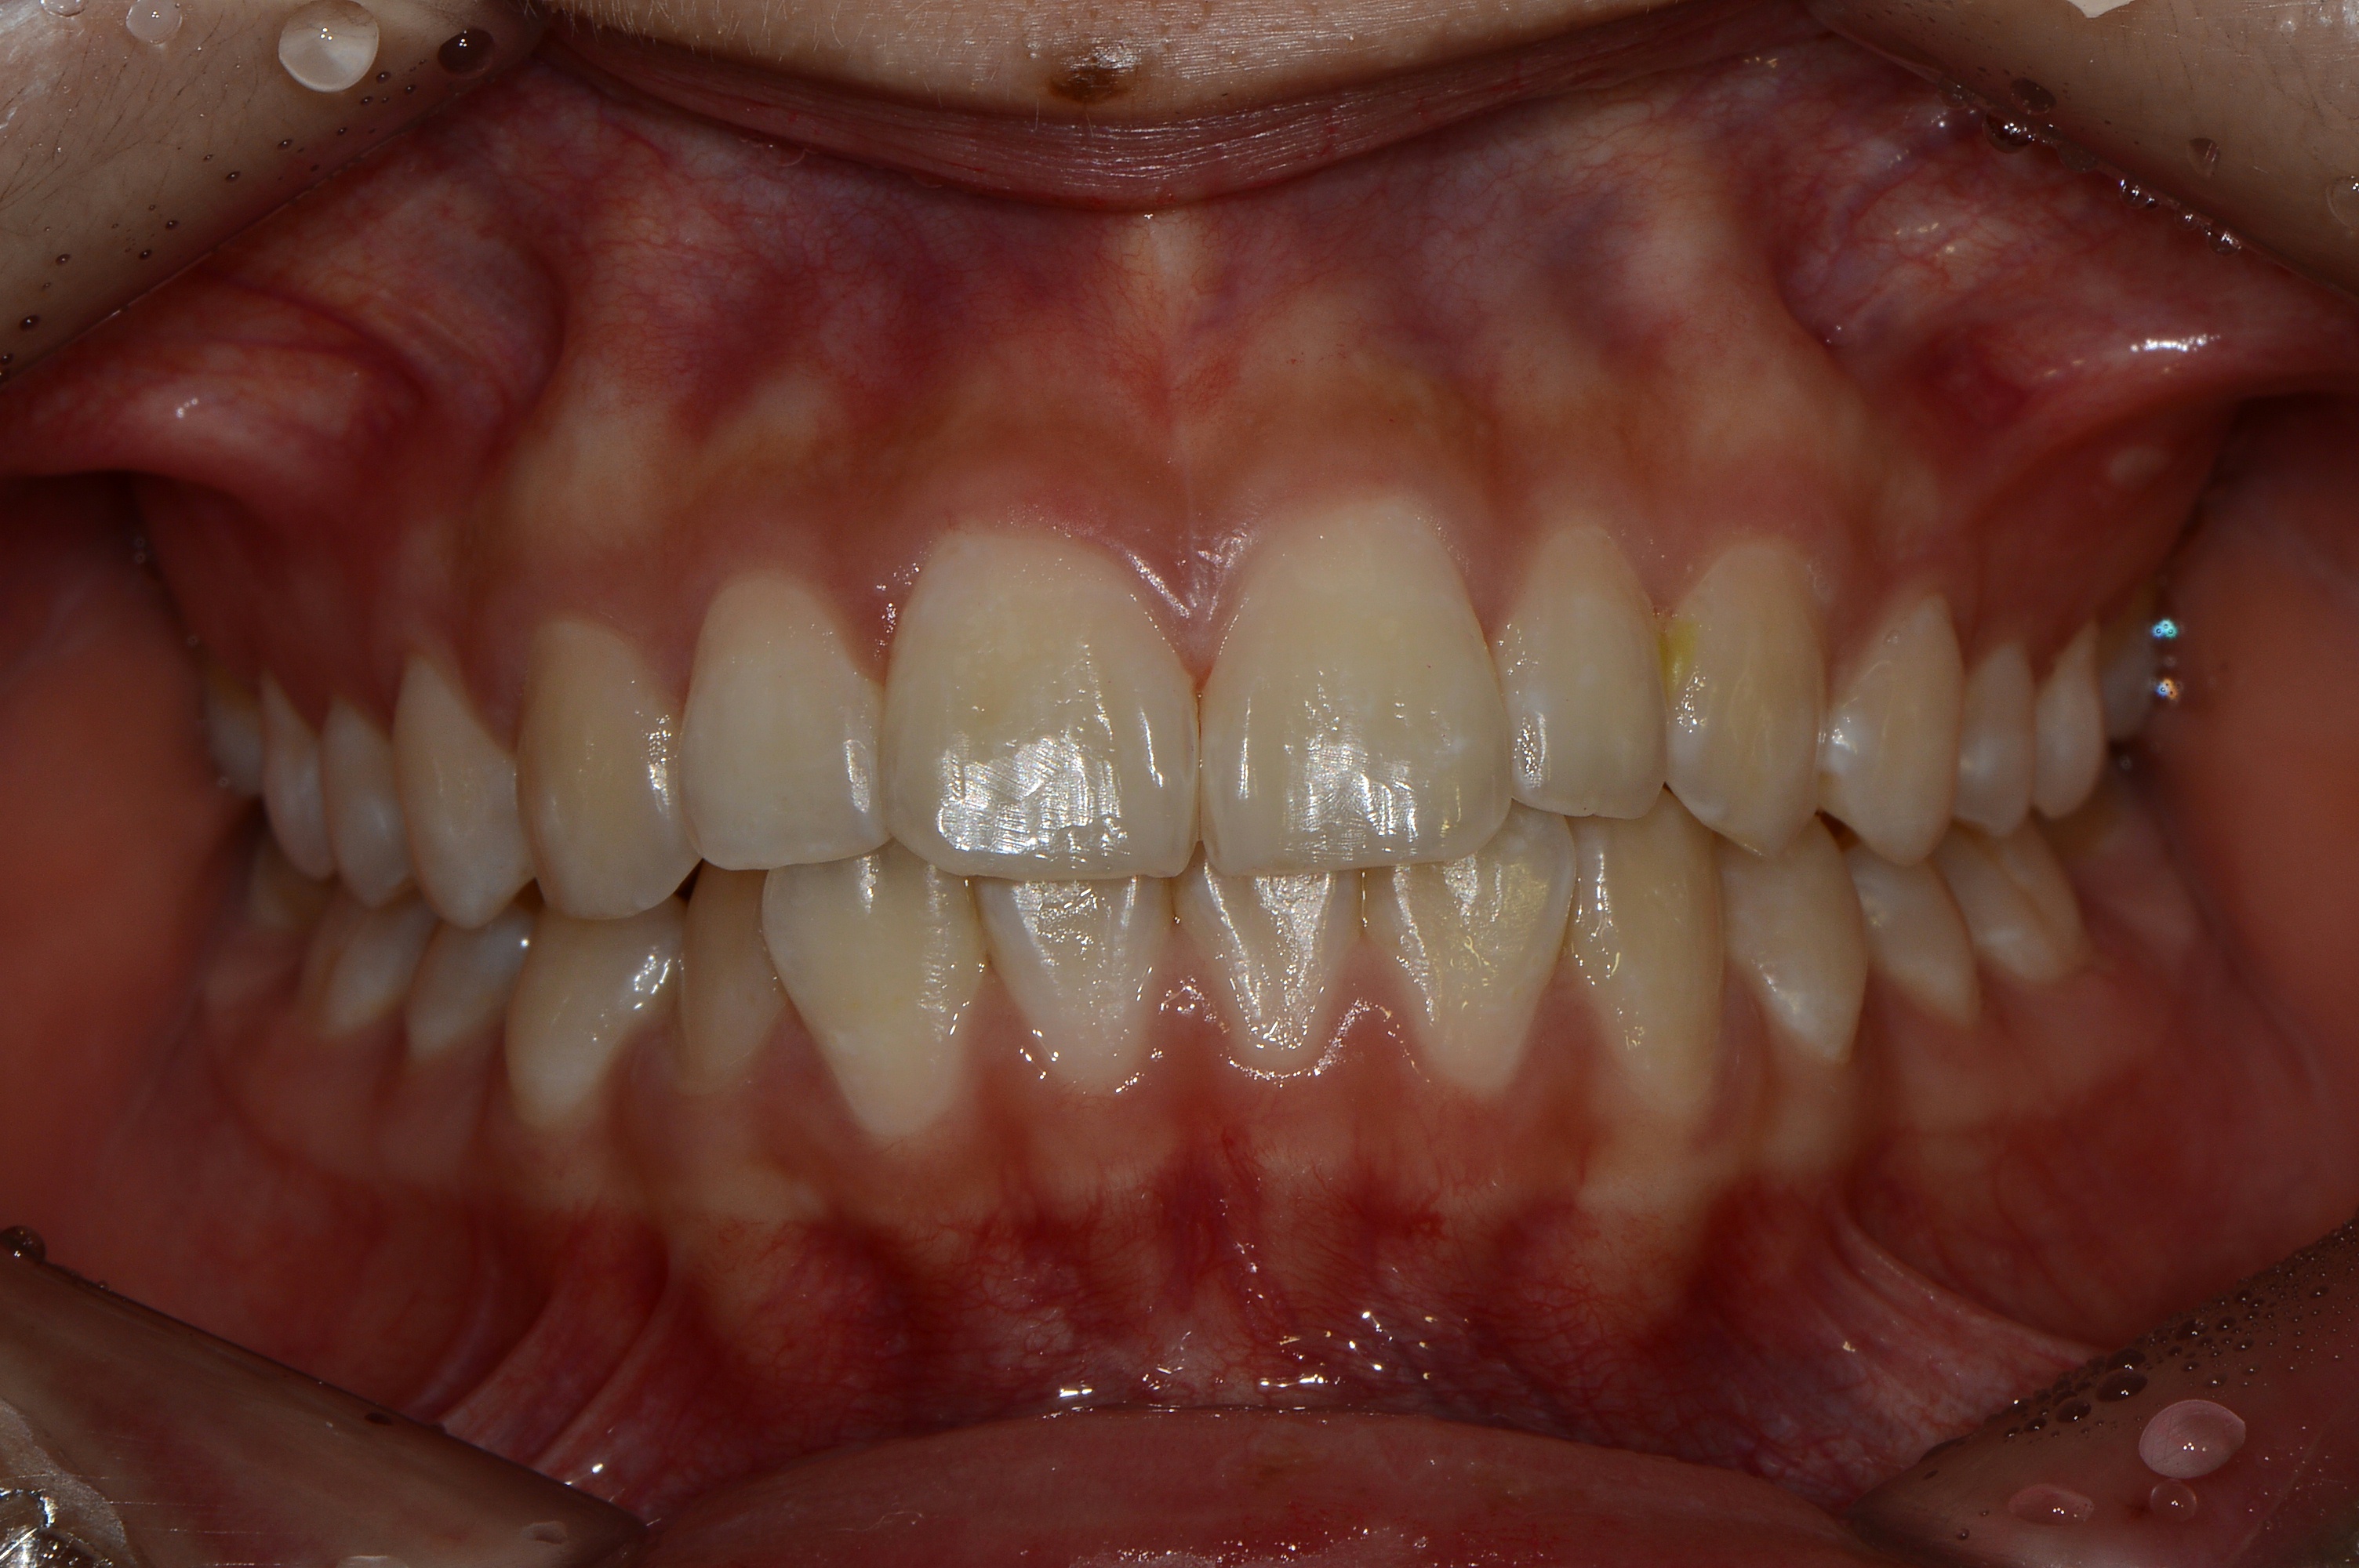

치료 전 사진입니다.